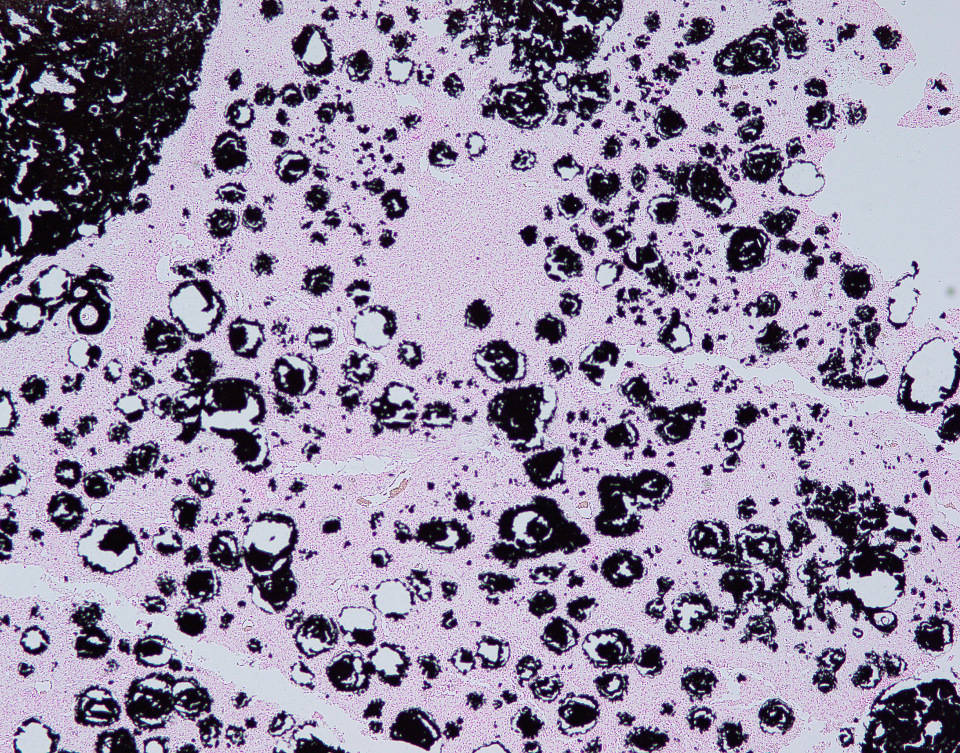

In this case, the lesions were confined to the right pelvic limb, with no evidence of involvement of other organ systems. A diagnosis of calcinosis circumscripta (tumoral calcinosis) was established based on the morphological, histopathological and immunohistochemical characteristics of the lesion. Mason trichrome, Von Kossa and Perl's Prussian blue stains were performed and were positive for the fibrous connective tissue (the first one) and the globular amorphous mineral (the last two). The presence of iron within the mineralized material is intriguing. Anecdotally, the African Green Monkeys on this facility tend to present hepatic iron overload and multifocal organ hemosiderosis. Extraskeletal osteosarcoma was considered as a potential differential. However, the cellular infiltrate was immunopositive for IBA-1 (histiocytes/macrophages) and immunonegative for SATB2 (osteoblastic origin, osteosarcoma), alpha-SMA38 (mature myofibroblast, smooth muscle tumor), SOX10 (neural crest origin, melanoma and certain soft tissue neoplasms), and S100 (amelanotic melanoma and certain soft tissue neoplasms). Based on clinical history of this animal, the lesion in this case most likely represents dystrophic calcification secondary to prior traumatic injury, as has been described in other nonhuman primates. To date, neither metastatic nor idiopathic calcification has been reported in this species.